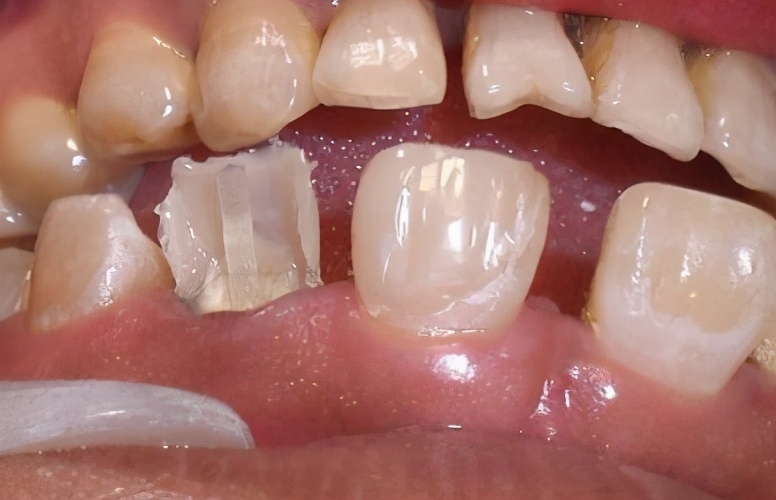

1、基牙腐烂

很多人认为只要套上牙冠,牙齿就“刀枪不入”了!实际上,就算套上牙冠,也极有可能发生蛀牙,戴牙冠发生蛀牙的常见部位通常在牙冠和牙齿龈线边的接合处。

如果出现这种情况,则需要及时去检查看是否需要更换新牙冠。